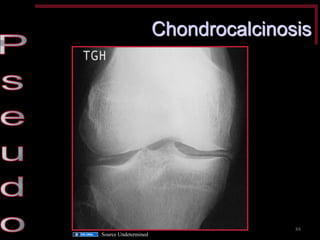

Hallmark X-ray Findings

Chondrocalcinosis = Pseudogout

Diagnosis •Common: elevated ESR, WBC •X-ray may show joint calcification •Joint fluid –Weakly positive birefringent crystals on polarized microscopy –Appear rhomboidal on regular light microscopy •Treatment: same as gout

Chondrocalcinosis